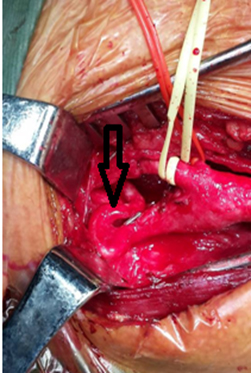

12.08.2015 г. хирургической бригадой (хирурги - Шатахян М.П., Айрапетян А.А., Петросян П.Р., анестезиолог - Мурадян А.Р.) под общей анестезией первым этапом была произведена резекция патологической деформации правой внутренней сонной артерии с реимплантацией в общую сонную артерию анастомозом конец в бок (рисунок №1).

Рисунок №1. Патологическая деформация правой ВСА (указана стрелкой) до и после коррекции.